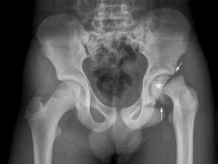

Knock Knees, medically termed as genu valgum, is a condition that affects

children, causing their knees to appear bent inwardly and the feet to be positioned apart.

Typically, it is a natural part of growth and development that resolves spontaneously by the

age of 6-7 years. However, certain factors such as injury, infection, vitamin D and calcium

deficiency, and genetic disorders may lead to the development of Knock Knees.